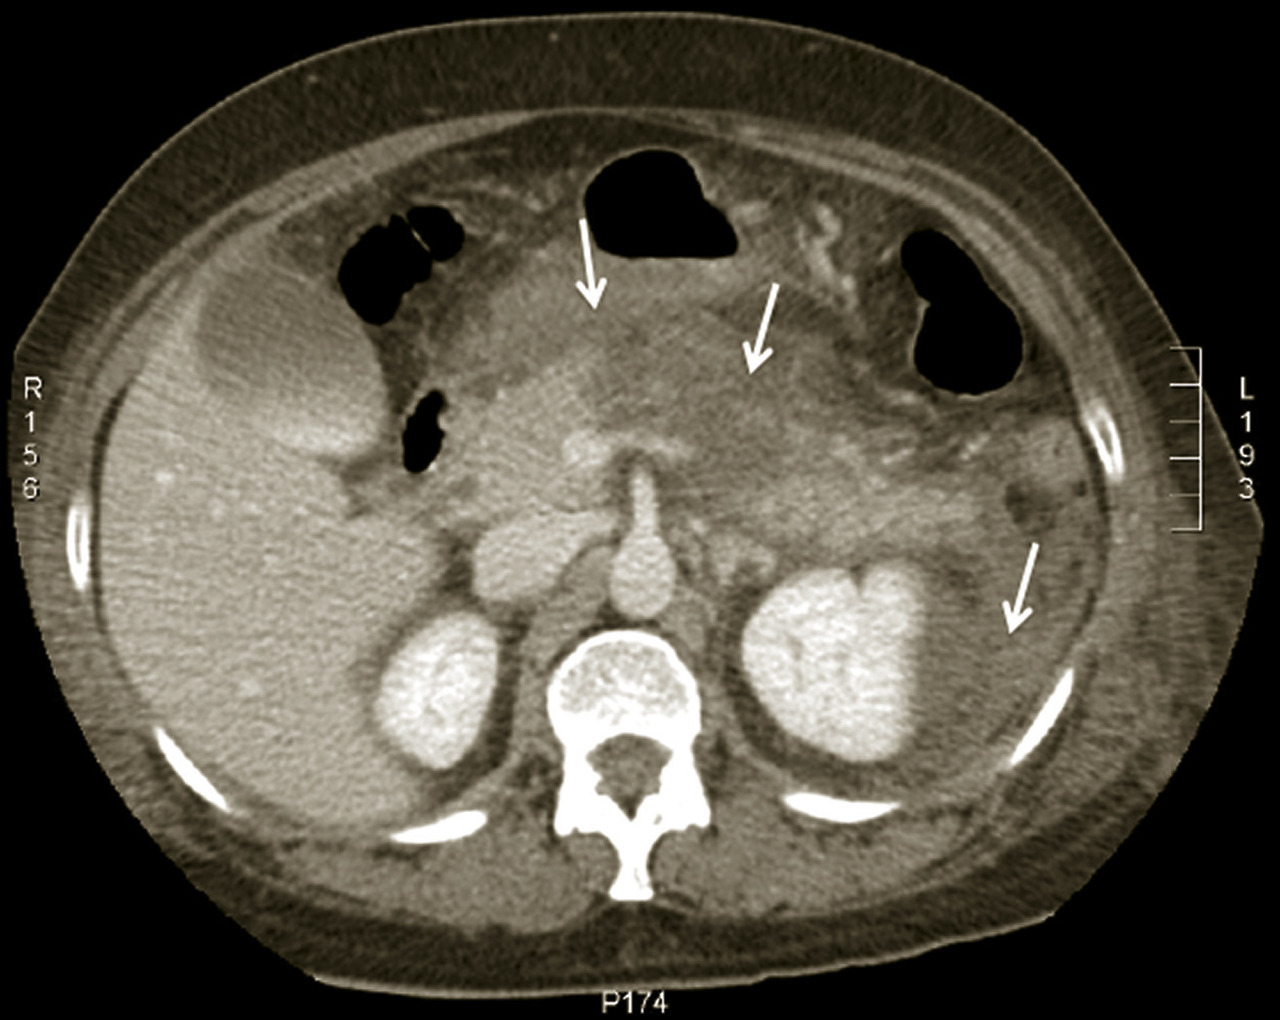

Le scanner abdomino-pelvien, voire thoraco-abdomino-pelvien, avec si possible injection de produit de contraste iodé (absence de contre-indication, notamment allergie à l’iode, insuffisance rénale sévère et grossesse), s’est progressivement imposé comme moyen d’imagerie diagnostique de première intention grâce à sa précision anatomique, sa rapidité de réalisation, son efficacité diagnostique dans la plupart des tableaux abdominaux urgents à l’exception de la pathologie aiguë annexielle gynécologique. C’est l’examen de choix dans les pancréatites aiguës après 48 à 72 heures d’évolution (fig. 4). L’irradiation et la néphrotoxicité des produits de contraste iodé limitent une application encore plus large chez l’insuffisant rénal, l’enfant, et la femme en âge de procréer (dosage préalable des ß-hCG pour s’assurer de l’absence de grossesse en cours), chez lesquels l’imagerie par résonance magnétique (IRM) abdomino-pelvienne est particulièrement indiquée, mais souvent plus difficile à obtenir en urgence.

Le diagnostic est évoqué devant une violente douleur épigastrique transfixiante, soulagée partiellement par la flexion du tronc (position en « chien de fusil »), une élévation franche de la lipasémie (supérieure à trois fois la valeur normale) et l’imagerie caractéristique au scanner. Deux causes dominent : la migration d’une lithiase biliaire et l’alcoolisation. L’examen clinique est pauvre contrastant avec l’intensité de la douleur et la gravité des signes généraux (marbrures, polypnée, pouls filant, hypotension artérielle). Un premier score de Ranson (clinico-biologique) supérieur à 3 affirme la sévérité de l’épisode. Le scanner (fig. 4), idéalement réalisé après 48 heures, permettra le calcul du score de Balthazar, fortement prédictif d’une complication grave (sur­infection des coulées de nécrose ou décès), en cas de valeur ≥ 4.